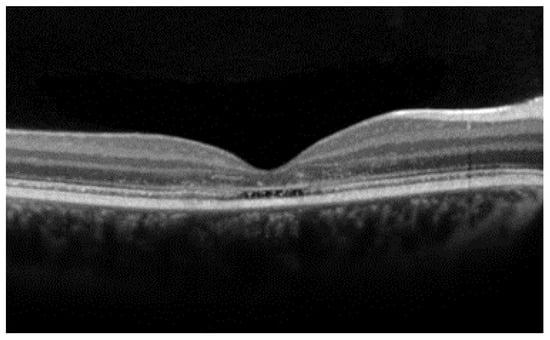

- The integrity of the EZ is the most closely linked factor to a decline in visual acuity. Its intensity, both in the affected areas and the surrounding regions, is attenuated in patients who show disease progression, and expansion of the disrupted EZ region is linked to a higher probability of visual acuity loss. Additionally, it is worth noting that many patients exhibit a central region with a preserved EZ, referred to as an optically preserved islet or OPI, which is associated with improved visual outcomes [29]. However, it is essential to recognize that EZ loss tends to occur in later stages and is typically associated with already significant visual impairment.

- Another noteworthy OCT biomarker is the measurement of ONL thickness, which can serve as an indicator of early photoreceptor degeneration. Irrespective of the clinical stage, BVMD patients exhibit reduced ONL thickness compared to healthy individuals [30]. Also, there is a correlation between ONL thickness and both BCVA and retinal sensitivity. Therefore, ONL thickness could prove to be a more valuable quantitative measure for assessing the anatomical loss of photoreceptors and the decline in macular function.

- Visual acuity is directly impacted by the presence of both vitelliform material and subretinal fluid. Eyes exhibiting vitelliform material typically demonstrate superior visual function, while the gradual reabsorption of this material, accompanied by the detection of subretinal fluid, is associated with a decline in visual acuity. Additionally, sensitivity, as measured by microperimetry, declines as vitelliform material is reabsorbed and subretinal fluid accumulates [31].